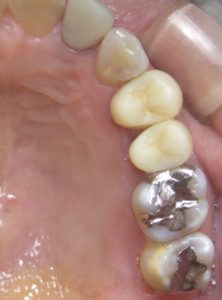

治療前

以前治療した歯の状態が悪くなり、当院を調べて来院されました。

インプラントを行った部位の歯は、神経の処置がしてあり、痛みはありませんでしが、2次虫歯が酷く、また骨(歯槽骨)が破壊されており、残念ながら抜歯を行いました。

骨の状態も悪く、そのままではインプラントが埋入できなかったので、GBR(骨を造る処置)を行って埋入しています。

インプラントの手前の歯は、根管治療を行いセラミックの被せ物をしました。

奥の歯2本は、それぞれ2次虫歯でしたが、神経は感染していなかったので、健康なエナメル質は温存して、セラミックとジルコニアで治療を行いました。